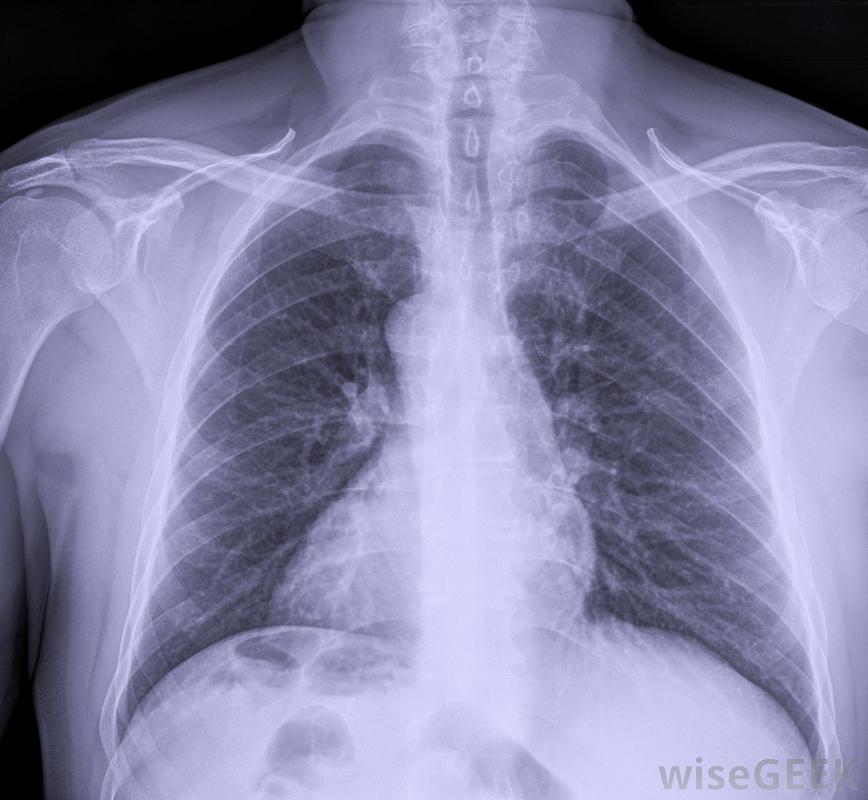

这些类型的静脉输液管可以由受过专门训练的护士、放射科医生或医师助理插入。此操作通常在无菌条件下在床边进行。在放置PICC线后,超声波用于显示上臂的大静脉放置,在使用该线之前,应进行胸部x光检查以确认放置位置是否正确。

将进行胸部X光检查,以确保PICC管线正确放置在使用前,